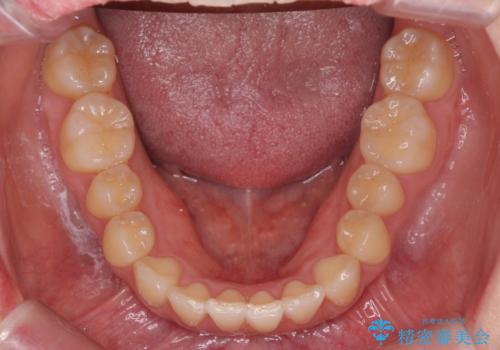

前歯がねじれている 奥歯を後ろに下げて歯を抜かずに並べました

上の奥歯を後ろに下げて前歯のねじれを治すスペースを確保しました。

奥歯を後ろに下げるために、矯正用インプラントを使用しています。